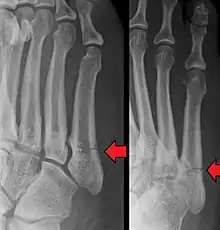

Jones fracture as seen on Xray

A Jones fracture is a broken bone in a specific part of the fifth metatarsal of the foot between the base and middle part[8] that is known for its high rate of delayed healing or nonunion.[4] It results in pain near the midportion of the foot on the outside.[2] There may also be bruising and difficulty walking.[3] Onset is generally sudden.[4]

The fracture typically occurs when the toes are pointed and the foot bends inwards.[6][2] This movement may occur when changing direction while the heel is off the ground such in dancing, tennis, or basketball.[9][10] Diagnosis is generally suspected based on symptoms and confirmed with X-rays.[3]

A person with a Jones fracture may not realize that a fracture has occurred. Diagnosis includes the palpation of an intact fibularis brevis tendon, and demonstration of local tenderness distal to the tuberosity of the fifth metatarsal, and localized over the shaft of the proximal metatarsal.

Diagnostic X-rays include anteroposterior, oblique, and lateral views and should be made with the foot in full flexion.